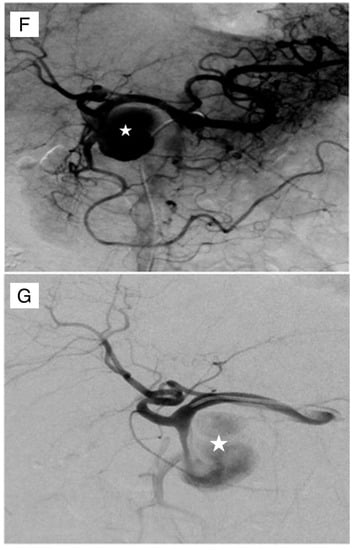

4. GDA Pseudoaneurysm Embolization